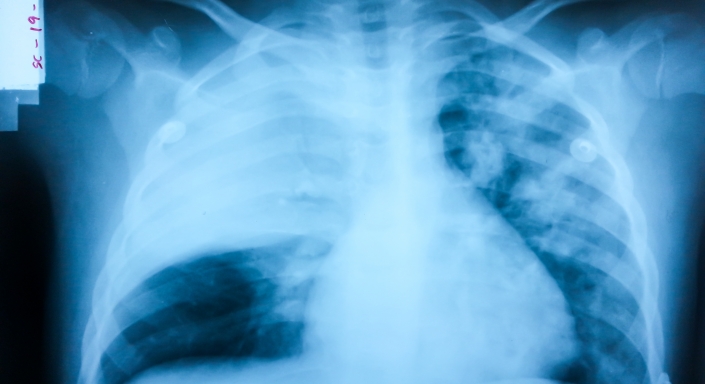

Пневмонию можно распознать по рентгену, прослушиванию в области грудной клетки, а также по определенной симптоматике. Больного мучает одышка, слабость, кашель, потеря аппетита, повышенная потливость вне зависимости от погоды и боли в груди. Болезнь может сопровождаться незначительным повышением температуры тела или, наоборот, ее критически низким значением.